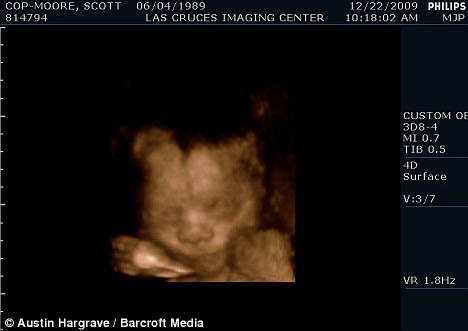

Малыш Скотта Мура и его супруга Томаса появится на свет через месяц. Фото: Daily Mail

Один раз мир уже удивлялся тому, что мужчина (правда, переделанный из женщины) смог забеременеть: в июле 2008 года житель штата Орегон родил девочку. Его рекорд не подпортил даже тот факт, что он - транссексуал. И вот теперь еще один американец - уроженец Калифорнии Скотт Мур - стал мужчиной №2, который вскоре родит. Малыш Скотта и его мужа Томаса появится на свет через месяц. Оба они - и Скотт, и Томас - когда-то были девушками, но потом подверглись операции по смене пола. Пара с нетерпением ожидает рождения ребенка, которого они собираются назвать Майлсом, сообщает Daily Mail.

Пара уже знает, что у них будет мальчик: своего малыша они планируют назвать Майлсом. Фото: Daily Mail